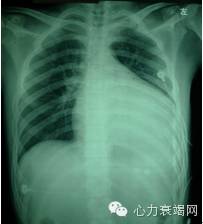

2年前心电图:

诊断: 心动过速心肌病

• 影像学提示:左心室显著扩大LV86mm,弥漫性运动降低,LVEF20%